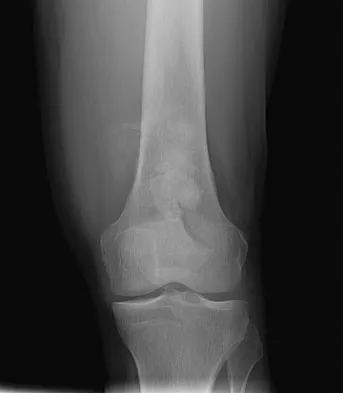

Which of the following choices best describes the fracture pattern shown in Figures 2a through 2c?

The fracture pattern shown in the radiographs is a fracture of the posterior column. The only line interrupted on the AP pelvis is the ilioischial line. The obturator oblique view shows that the iliopectineal line is intact as is the outline of the posterior wall. The iliac oblique view shows an interruption of the ilioischial line and an intact anterior wall. Therefore, this fracture is a fracture of the posterior column. Letournel E, Judet R: Fractures of the Acetabulum, ed 2. Berlin, Germany, Springer Verlag, 1993.

- Matta J: Surgical treatment of acetabular fractures, in Browner BD, Jupiter JB, Levine AM, et al (eds): Skeletal Trauma, ed 3. Philadelphia, PA, WB Saunders, 2003, vol 1, pp 1009-1149.